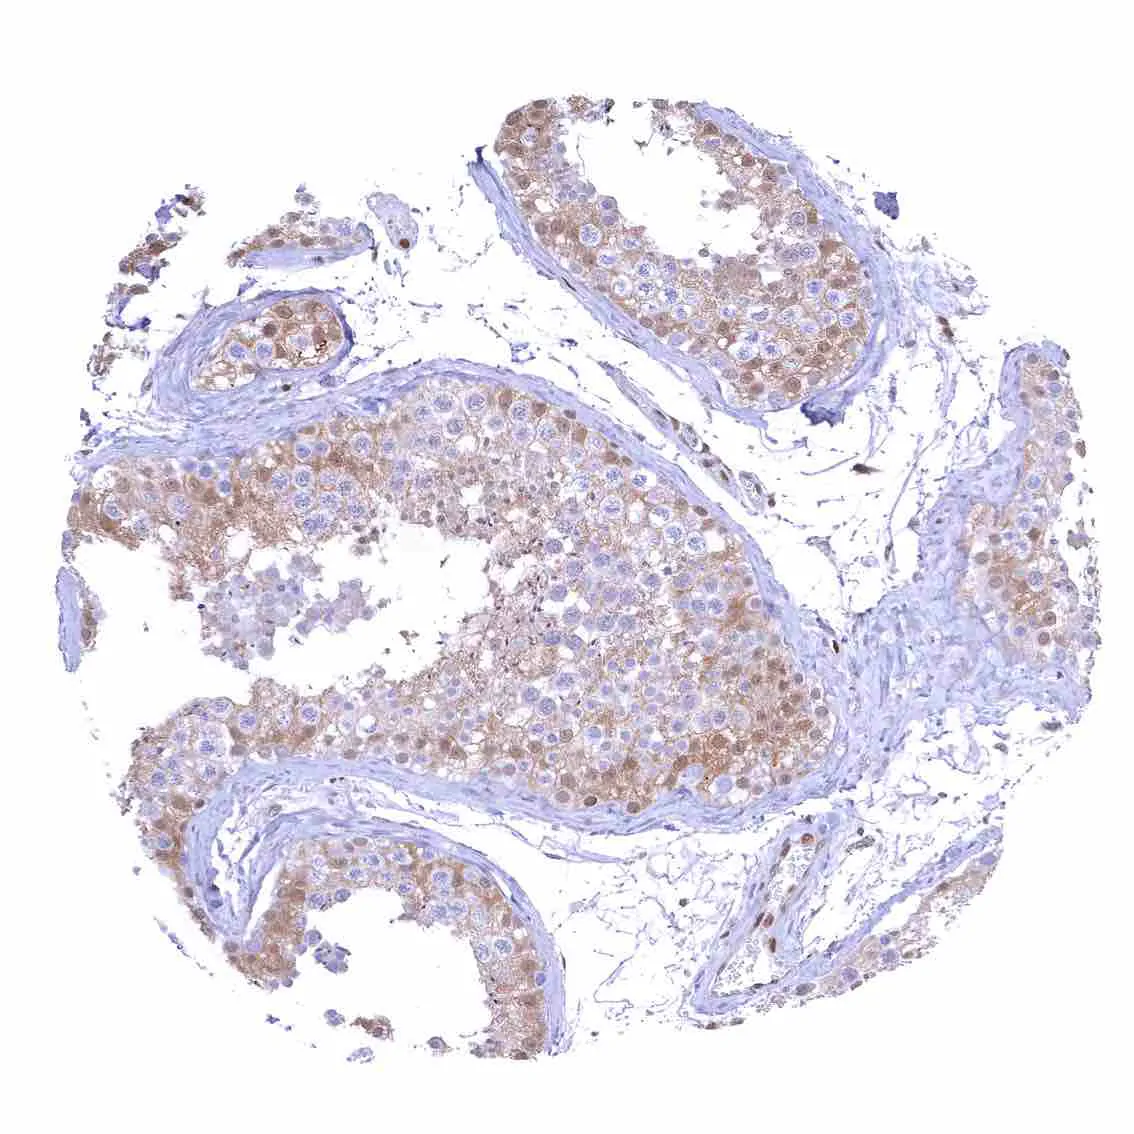

Testis – Weak to moderate nuclear p27 staining of a subset of cells (predominantly Sertoli cells).